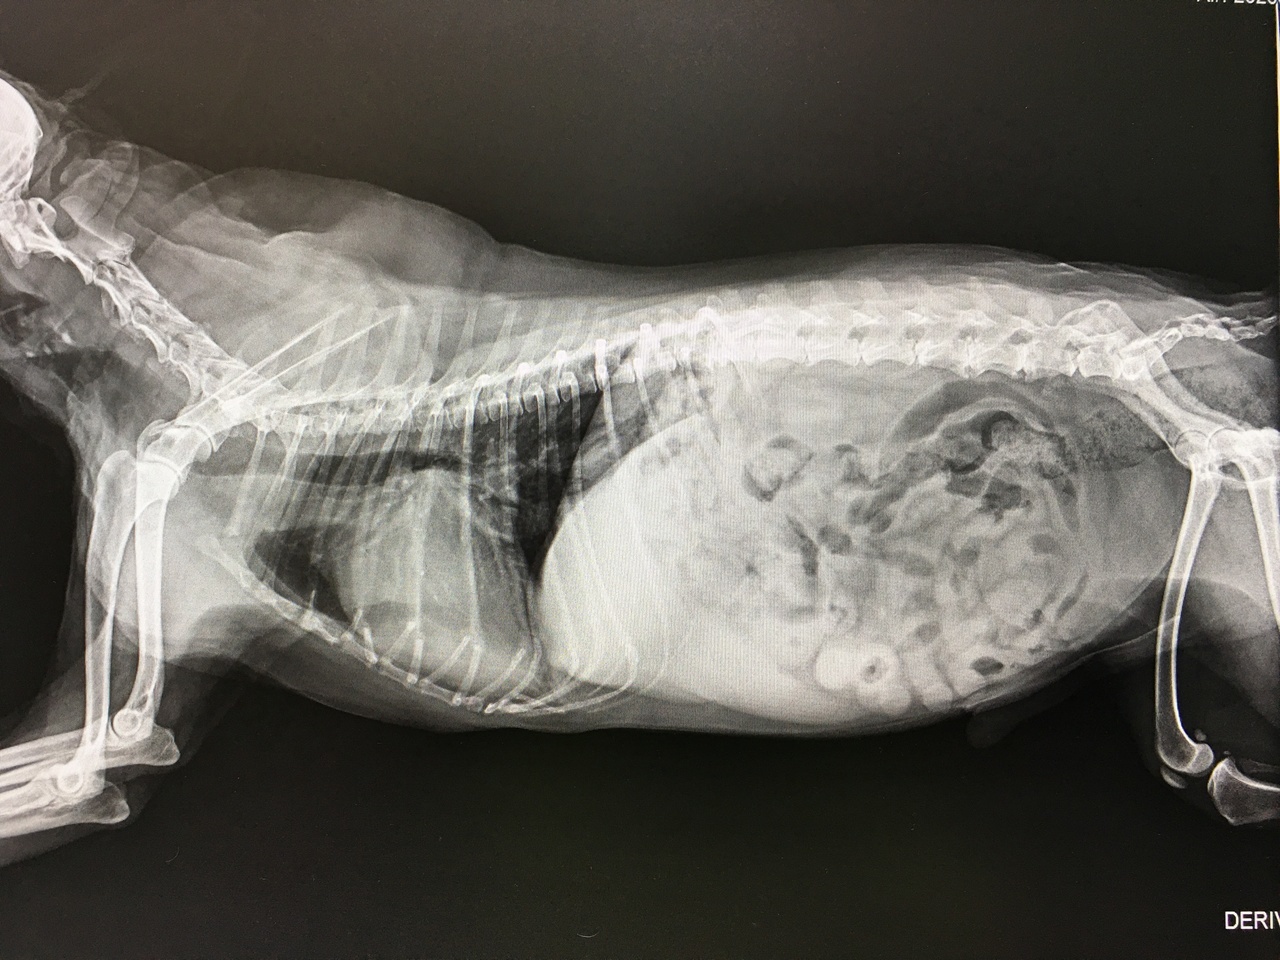

レントゲン検査で心臓の大きさを評価したり、大きくなった心臓に気管が圧迫されていないかをチェックします。